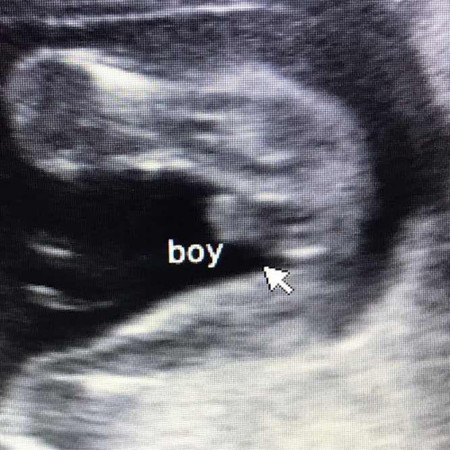

Gender @ 6months

Sure na po kaya gender ni baby @6months? Sabi ni OB boy daw pero yung maghihilot samin sabi ay girl daw si baby? Kung titignan yung picture may lawit si baby e

Magbasa paMalalaman nyo po yan sa sunod na followup ultrasound nyo po if nagdodoubt po kayo sa ob nyo po lalo na sa CAS, or pra mas sure pde po kayo mag pa 3d/4d po.. sakin po kasi naaninag na upon 4mons. Ms mdli po mkta ang gender ng bby boy

ganyan sakin hehe nun una nagdalawang isip si doctora, pero nun pagbalik ko checkup doon na mas klaro na boy tlaga hehe